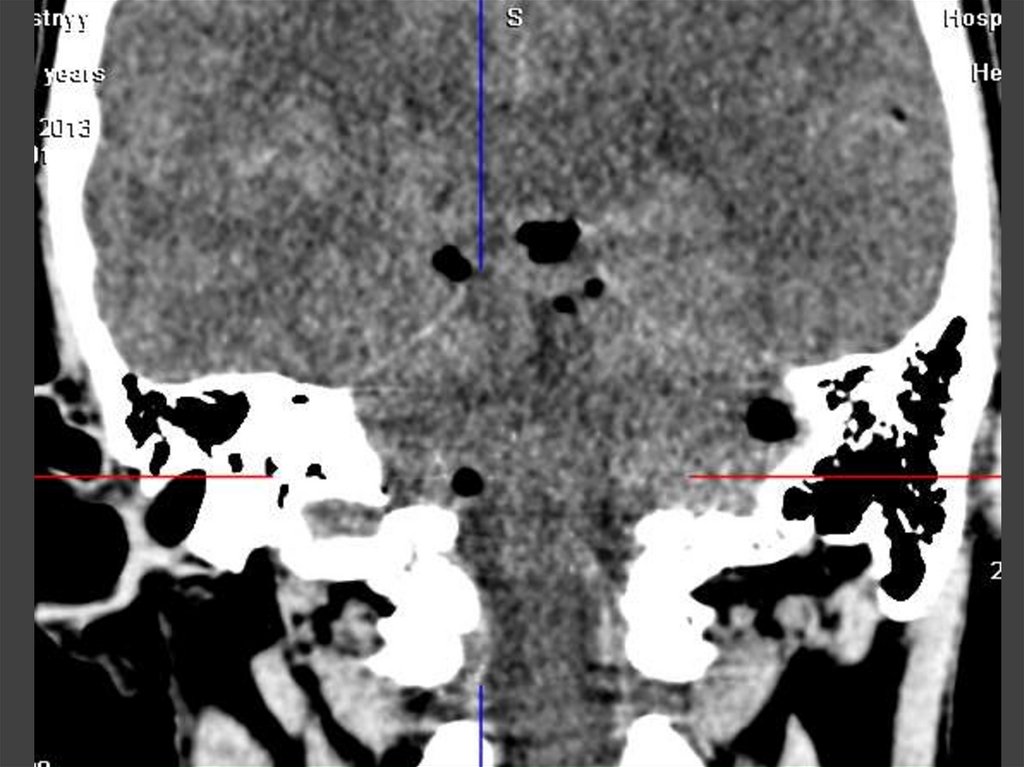

ОСТРЫЙ ОТОМАСТОИДИТ

Неосложненный

отомастоидит –

патологическое содержимое

внутри ячеек сосцевидного

отростка

Осложненный - разрушение

перегородок,наружной и

внутренней кортикальной

пластинок сосцевидного

26.

27.

28.

29. ОСТРЫЙ ОТОМАСТОИДИТ